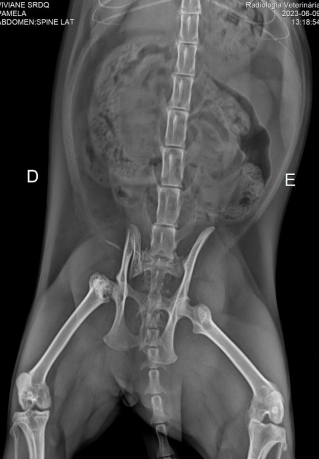

No começo de junho, apesar das medidas de segurança, nossa gatinha Viviane sofreu um acidente e precisou de atendimento veterinário de emergência. O resultado foi uma fratura de íleo direito e disjunção sacroilíaca esquerda (ou seja, a base da coluna vertebral (osso sacro) e os ossos da bacia (ilíacos).

Pré-operatório: